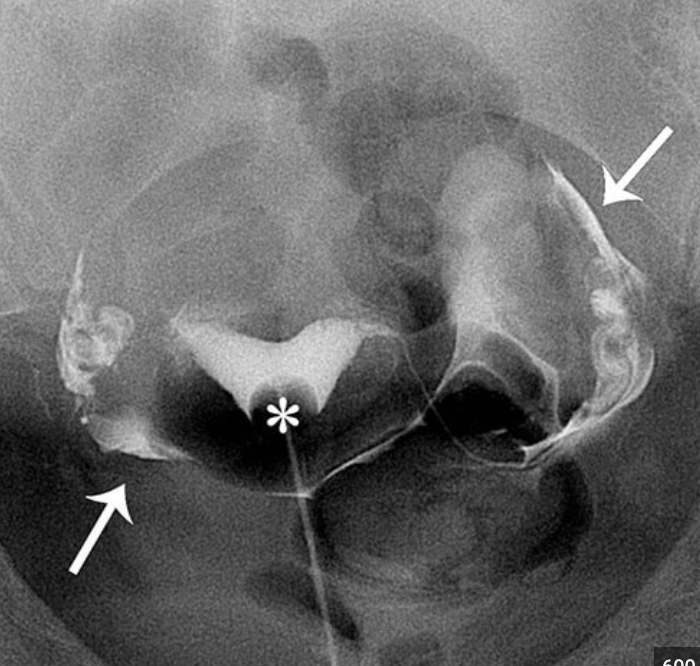

Hysterosalpingogram

Commonly used for investigation of infertility/miscarriage

Assess normal shape of uterine cavity, patency of fallopian ducts, free spill of contrast into interperitoneal space

A hysterosalpingogram (HSG) isan X-ray dye test used to diagnose problems related to fertility.

Hysterosalpinogram

Used to assess patency of fallopian tubes